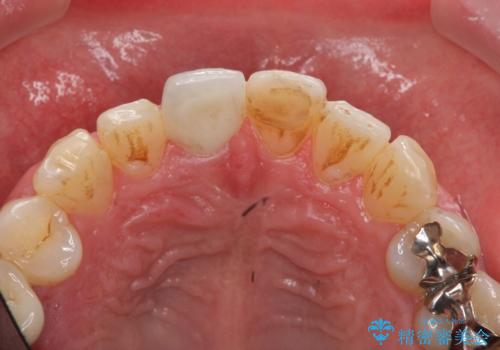

前歯の変色を改善!セラミック治療

- 前歯の変色が気になり審美障害の改善を求めて来院されました。

根管治療に伴う歯の色調変化はよく見られる所見です。

セラミッククラウン製作を行い審美性の改善を計画します。

- 15.4万円(仮歯・ファイバーコア・ジルコニアクラウン)費用は治療当時の料金となります

周囲の歯の色調に合わせた、自然なセラミック治療を行うことができましt。